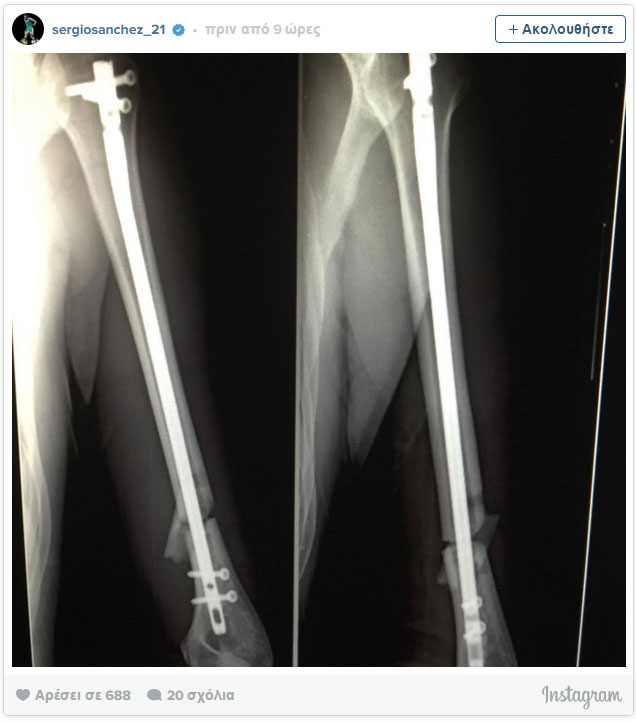

Ο Ισπανός αμυντικός ανέβασε στο Instagram την ακτινογραφία του και έγραψε:

«Βλέπω το τέλος του τραυματισμού μου. Πρέπει να επιστρέψω άμεσα».